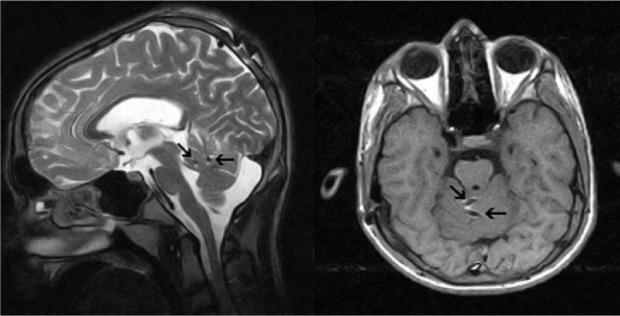

With the aim of comparing autonomic functions as they relate to interhemispheric modulatory influences during therapeutically indicated stereotactic cerebellar stimulation, we have performed bilateral electrodermal activity measurement and calculations of pointwise transinformation (PTI) in a patient with cerebral palsy. Measurement was performed during therapeutic deep cerebellar stimulation in two cerebellar areas in anterior cerebellar lobe-culmen (left electrode) and central lobule-superior cerebellar peduncle (right electrode).

The results indicate that information transference (PTI) is able to distinguish the states related to specific cerebellar stimulations and that lowest levels of the PTI have been found during stimulation of the central lobule-superior cerebellar peduncle (electrode deepest contact 1), indicating a significantly increased level of inhibition between the left and right sides.